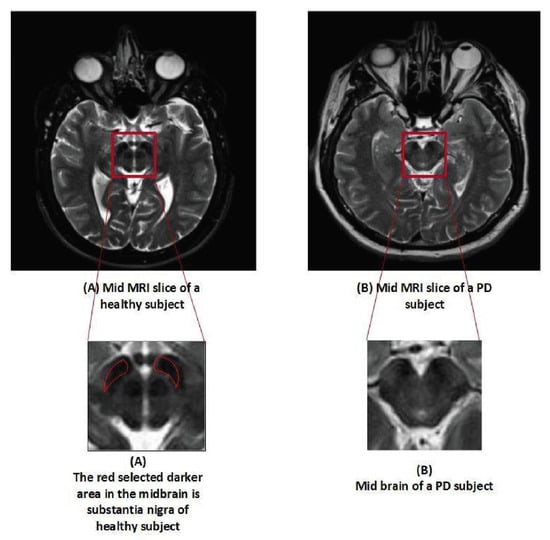

The dataset utilized in this analysis was made available by the PPMI. The PPMI is a multi-study facility with the goal of discovering trustworthy biomarkers and performing an early Parkinson’s disease diagnosis. Additionally, it is the project with the greatest data, which includes a sizable number of clinical, imaging, and biological samples. It is claimed that PPMI offers the largest dataset of its kind, and their samples are known as the benchmark of PD for research purposes across the globe [37]. A total of 500 samples (T2 weighted MR scan) were obtained in Digital Imaging and Communications in Medicine (DICOM) format with the followed parameters, Plane=AXIAL Acquisition Flip Angle = 150.0 degree, Matrix X = 228.0 pixels, Matrix Y = 256.0 pixels, Matrix Z = 54.0, Slice Thickness = 6.0 mm, Pulse Sequence=Spin echo, Pixel Spacing Y = 0.9375 mm, Pixel Spacing X = 0.9375 mm. The data contained 250 numbers of PD and 250 HC samples, balanced data. Dataset is used in such a way that 70% is used for training, 20% for testing, while 10% for validation. The dataset is available on (http://www.ppmi-info.org). Table 2 represents the details of the subject in terms of gender and age, while Figure 2 shows the difference between the MRI scan of a healthy subject and Parkinson’s patient.

Figure 2.

Slices of an MRI scan of an HC and PD patient.

The MR images were initially stored in the DICOM format and then converted into JPEG using publicly available software known as DICOM to JPEG. Each subject’s data consisted of 45 slices, and only slice number 22 was collected per subject since this slice provides the accurate image of the substantia nigra in PD class. Substantia nigra is a structure in the mid-brain area that controls movement and motor coordination. Dopamine is a substance that is produced in this area and is employed as a signal transmitter. This sends signals about movement and coordination to the brain and other parts of the body. A stack was created by combining slice number 22 from all the subjects. To align the images, intensity-based image registration was carried out using the OpenCV library on the stack. Image registration is the procedure of lining up scans of the brain or other pertinent regions taken from people with Parkinson’s disease. Using image registration techniques, this alignment establishes the spatial relationship between the pictures, enabling a consistent and uniform analysis. By ensuring that the pictures are in a uniform coordinate system, image registration eliminates variances brought on by changes in patient placement or scanning procedures. The primary objective of image registration was to eliminate unwanted and irrelevant information, which could lead our model to learn unnecessary and redundant features. For obtaining a perfect image of substantia nigra, the mid-brain section was cropped using the freehand region of interest (ROI) technique with a window size of 33 × 33. Freehand ROI was used for cropping because the size of the specific organ varies in different patients, and, instead of using fix ROI cropping, the freehand region of interest (ROI) technique provides us better control in cropping the exact position of the organ. This image was the final input to the CNN model. Figure 3 provides a visual representation of the preprocessing steps.